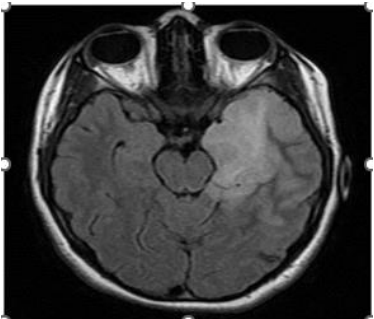

Figure 1: 17-year-old female patient with anti-NMDAr encephalitis (seropositive). Cerebral MRI, FLAIR sequence: left temporo-insular hyper signal.

Brain MRI often objectified parenchymal abnormalities (86.7% of cases), which were similar to those reported in the literature [25, 51], including isolated temporal lesions (36.6% of cases). They were more bilateral than unilateral. Extra limbic radiological abnormalities were found in half of the cases. The most affected localisations are mainly the frontal lobe, the basal ganglia, and rarely other structures, such as the insula, parietal lobe, occipital lobe, meninges and white matter are affected. These extra limbic anomalies have been reported in the literature at a lower frequency than ours (40% of cases) [51]. Graus et al. included bilateral temporal involvement (in T2 and FLAIR) in the criteria for defined autoimmune encephalitis [23]. Unilateral temporal impairment would be possible. However, in this case, Graus et al. required the presence of antibodies to classify it as autoimmune encephalitis because other etiologies, such as glioma, seizures, and HSV1, could cause a unilateral temporal hyper signal [23].